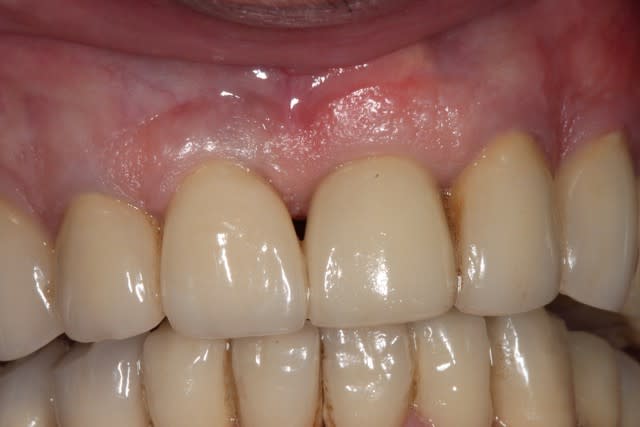

(petite précision c'est une photo à + de 2 ans post prothèse)

photo de controle vue vestibulaire et occlusale 8 mois post chir

puis à 2 ans post op

on constate que contrairement à la 11 surlaquelle il y a un affaissement de l'os vestibulaire

sur la 21 le volume est préservé

Si je peux me permettre, la 11 semble plus naturelle, car le zénith gingival est plus ovoide. La 21 possède certe plus de volume de tissu en vestibulaire, mais le collet gingivale est trop coronaire, effet de dent trapue.

L'ensemble est par contre sympa.